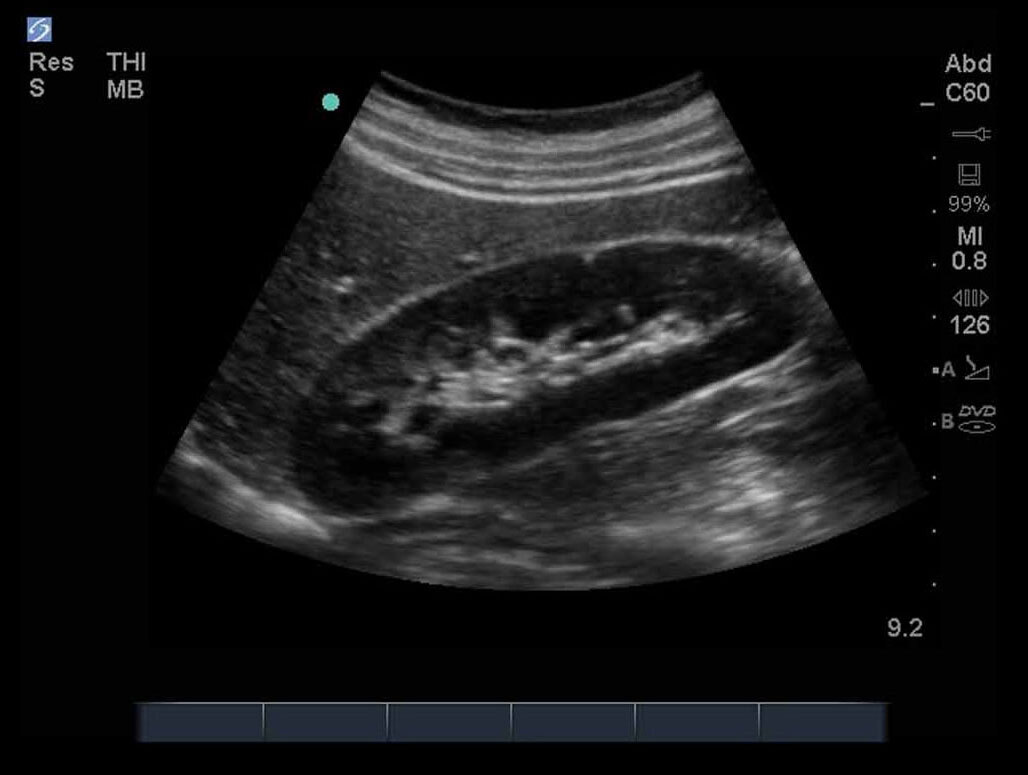

FAST 右上四半部 (RUQ) 1 画像

M-Turbo:FAST検査、右上四半部 1。